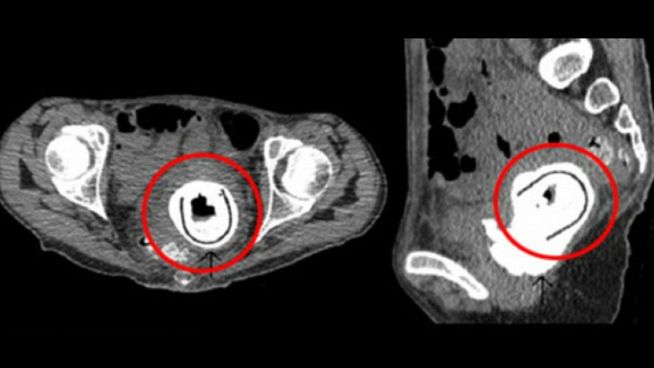

¡Encuentra un juguete sexual en su vagina diez años después!

SIN FONDO

Una mujer ha encontrado un juguete sexual en su vagina... el juguete sexual tuvo que retirarse mediante cirugía y hoy en día la mujer ya figura en...